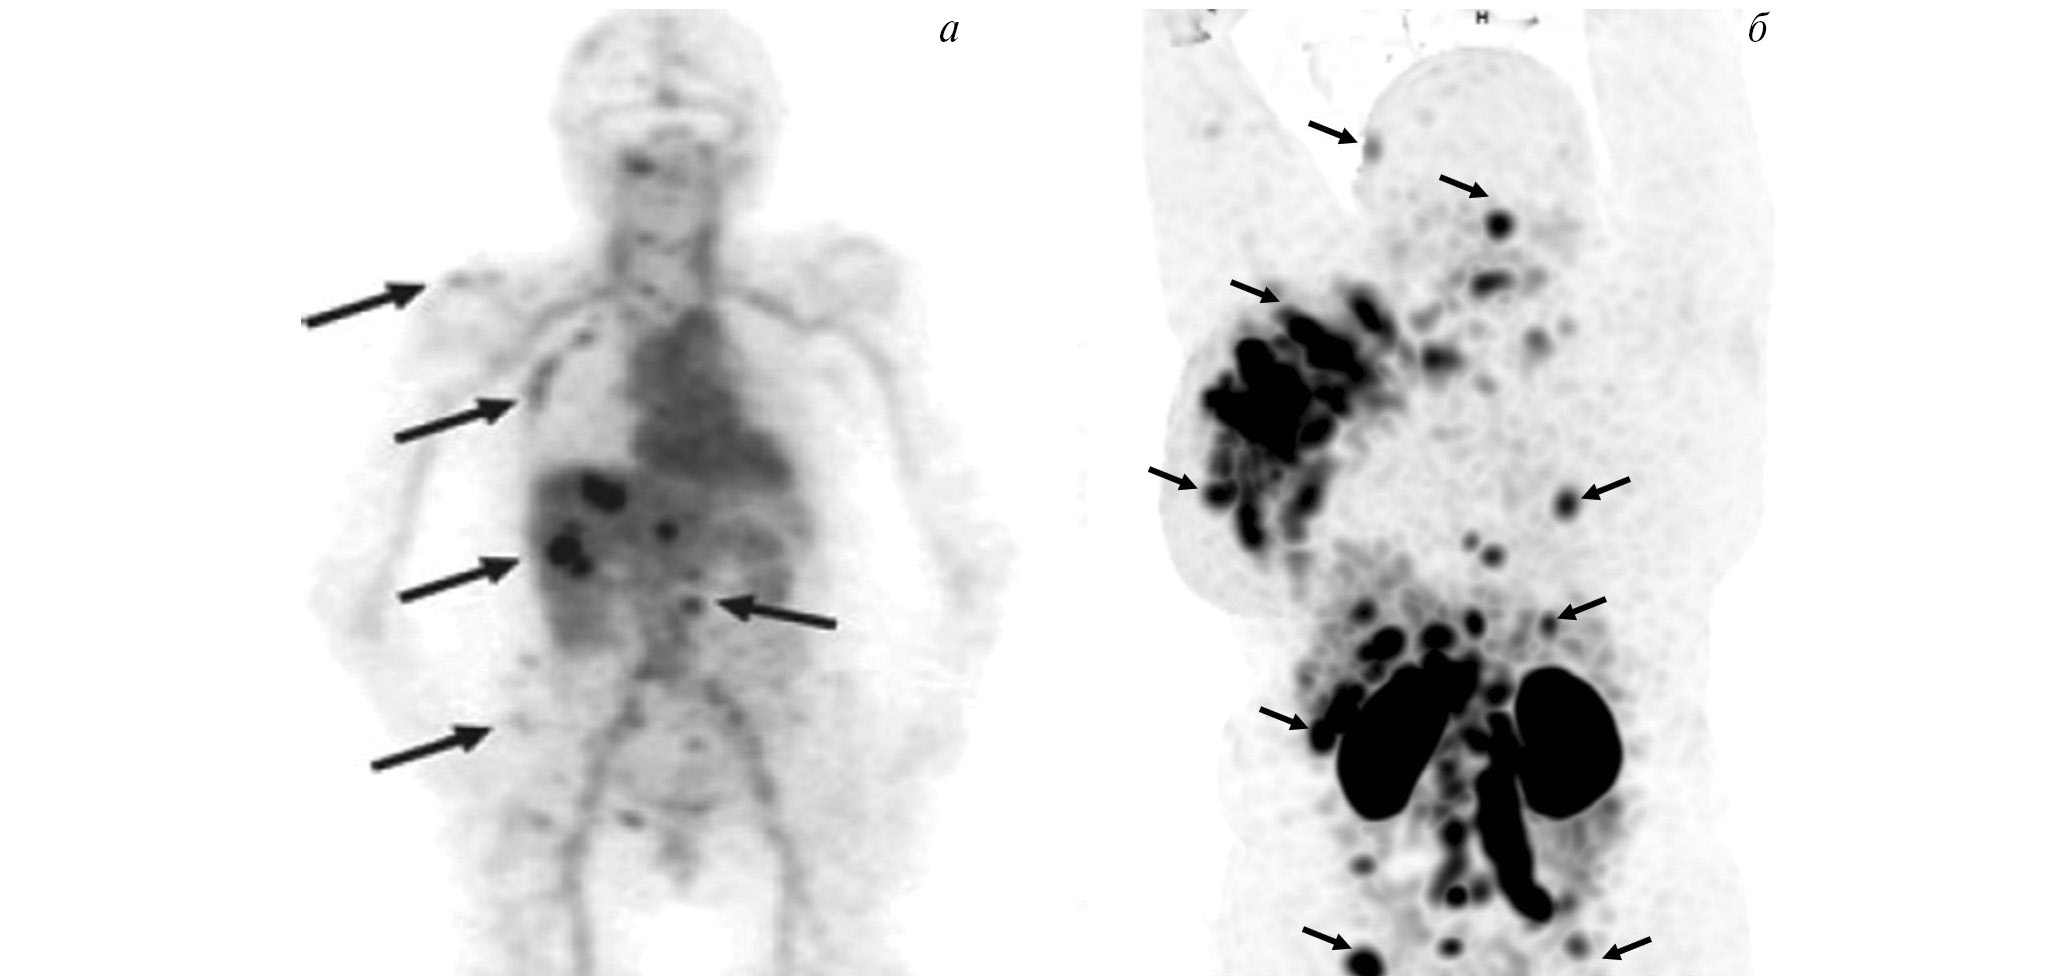

В НИИ онкологии Томского НИМЦ завершены первые фазы клинических исследований нескольких меченных технецием-99м каркасных белков (DARPin, ADAPT, Affibody), обладающих высокой аффинностью к рецептору эпидермального фактора роста второго типа (HER2/neu). Все препараты показали хорошую эффективность определения гиперэкспрессии рецептора HER2/neu при раке молочной железы и стадировании заболевания (рис. 1) [10, 11]. Кроме того, установлена возможность проведения ОФЭКТ/КТ с препаратами на базе скаффолдов для оценки эффекта терапии (рис. 2). Помимо основы РФЛП для диагностики злокачественных новообразований, каркасные белки могут служить вектором доставки при создании таргетных соединений для лечения злокачественных новообразований с гиперэкспрессией рецептора HER2/neu [13].

Рис. 1. ПЭТ-изображение пациентки с HER2/neu-позитивным раком молочной железы, выполненное через 5 суток после введения 89Zr-транстузумаба (a), стрелками обозначены метастазы в печень и кости [12]; ОФЭКТ-изображение пациентки с HER2/neu-позитивным раком молочной железы через 2 ч после введения 99mTc-ADAPT6 (б), стрелками обозначены первичная опухоль, метастазы в лимфатические узлы, печень и кости